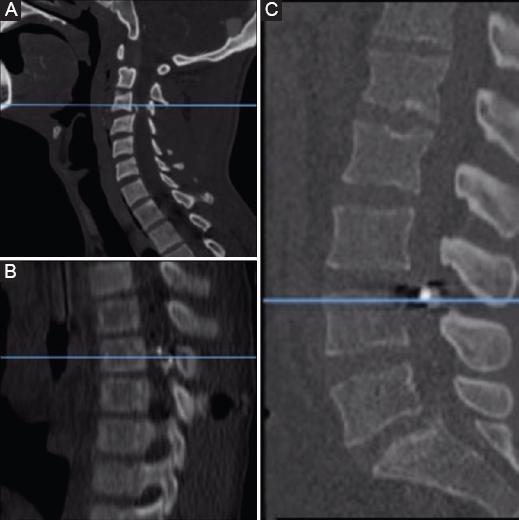

The approach to a patient with a spine injury secondary to a gunshot wound should always follow the ATLS (advanced trauma life support) protocol before managing any kind of spinal pathology in the trauma patient11. The initial radiologic evaluation should start with two plane radiographs (Fig. 1) even though many centers today advocate the minimal utility of radiographs and prefer using the computed tomography (CT) scan as the initial radiographic study (Fig. 2). CT scan with reconstruction should be considered in every gunshot injury to the spine to determine the integrity of the spine elements. In our center, we do not routinely request an MRI in gunshot spine injuries. The use of magnetic resonance imaging (MRI) in patients with gunshot injuries to the spine remains controversial. Dedini et al. reported that the use of MRI in a patient with retained projectile fragments requires knowing their composition; concluding that alloy and copper fragments are safe to continue the study, while steel is not12.

Figure 2 Lateral radiographs. A: cervical. B: thoracic. C: lumbar. Spine with gunshot injuries.

The thoracic spine had the highest frequency of injuries in our series with 26 patients (48.5%), followed by the lumbar spine with 25 patients (45.5%), three patients (6%) with cervical spine injuries, and one patient with a sacral injury (1.81%). Injury distribution was similar to the reported in the literature by Benzel et al.13 and by Simpson et al.11, with the thoracic spine having the highest frequency of injuries. Of the total patients assessed in our study, 30 (54.53%) presented with a neurological injury. The prevalence of neurological injury is similar to the data reported in the literature. Kupcha et al. in their study of 28 patients reported that 75% presented with neurological injury14. According to Waters and Adkins in their prospective study of surgical treatment for gunshot wounds to the spine, there is evidence of recovery in patients with incomplete deficits, especially in the T12 to L4 region, so decompression should be performed as soon as possible in a patient with incomplete injury. The general consensus in patients with complete spinal cord injury is that there is no neurological benefit with surgical intervention15. In our patient series, only one patient was surgically managed: 26 y/o male patient with an L1 fracture (Fig. 4) and an incomplete neurological injury (ASIA B). He was taken to surgery within <24 h of evolution. During follow-up, the patient showed no neurological improvement. Patients without neurological deficit were treated with broad-spectrum intravenous antibiotic therapy, wound debridement and immobilization according to the level of injury (e.g., Philadelphia collar, Jewett, or Taylor brace) (Fig. 5).

Figure 4 CT scan images of a 26 y/o male patient (ASIA B) showing vertebral body compromise and medullary canal involvement at L1.